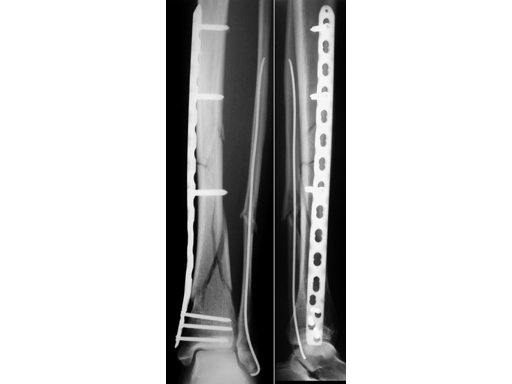

32-year-old woman, closed fracture type 42-C3 with minimal soft-tissue injury, after skiing accident.